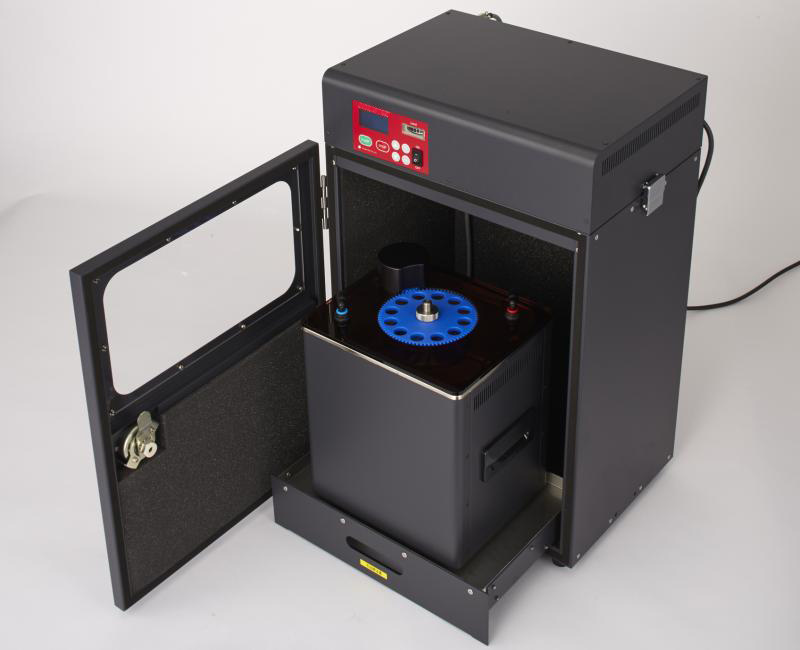

HistoSonics、世界初の「Edison®ヒストトリプシー・システム。SONOBIO Split-type Ultrasonic Homogenizer/Sonicator。Model 3000 - Ultrasonic Homogenizers - Sonicators。ミルキークイーン令和6年兵庫県産玄米15kg。PACIFIC BIOSCIENCE LABORATORIES クラリソニック(ホワイト)数回使用後、自宅保存していた中古品です。★ コメントからご相談ください-----------------------------------------・バラ売り可能・他の出品商品とまとめ買いでお値引き可能★ 検索用-----------------------------------------EL.COSMETICS分類: 洗顔・ボディーブラシcolor: WHITEブラシ機能: 洗顔ブラシ#PACIFICBIOSCIENCELABORATORIES#PACIFICBIOSCIENCELABORATORIESタイプ···美顔器部位···顔電源方式···充電式防水···防水機能ありタイプ···クレンジングブラシ部位···顔部位···全身部位···顔。DeltaTime TCSPC Lifetime Kit - HORIBA。小さい傷はあるかもしれませんが、目立った傷や汚れはありません。[美品] YA-MAN ヤーマン フォトシャイン IS-101N スチーマー